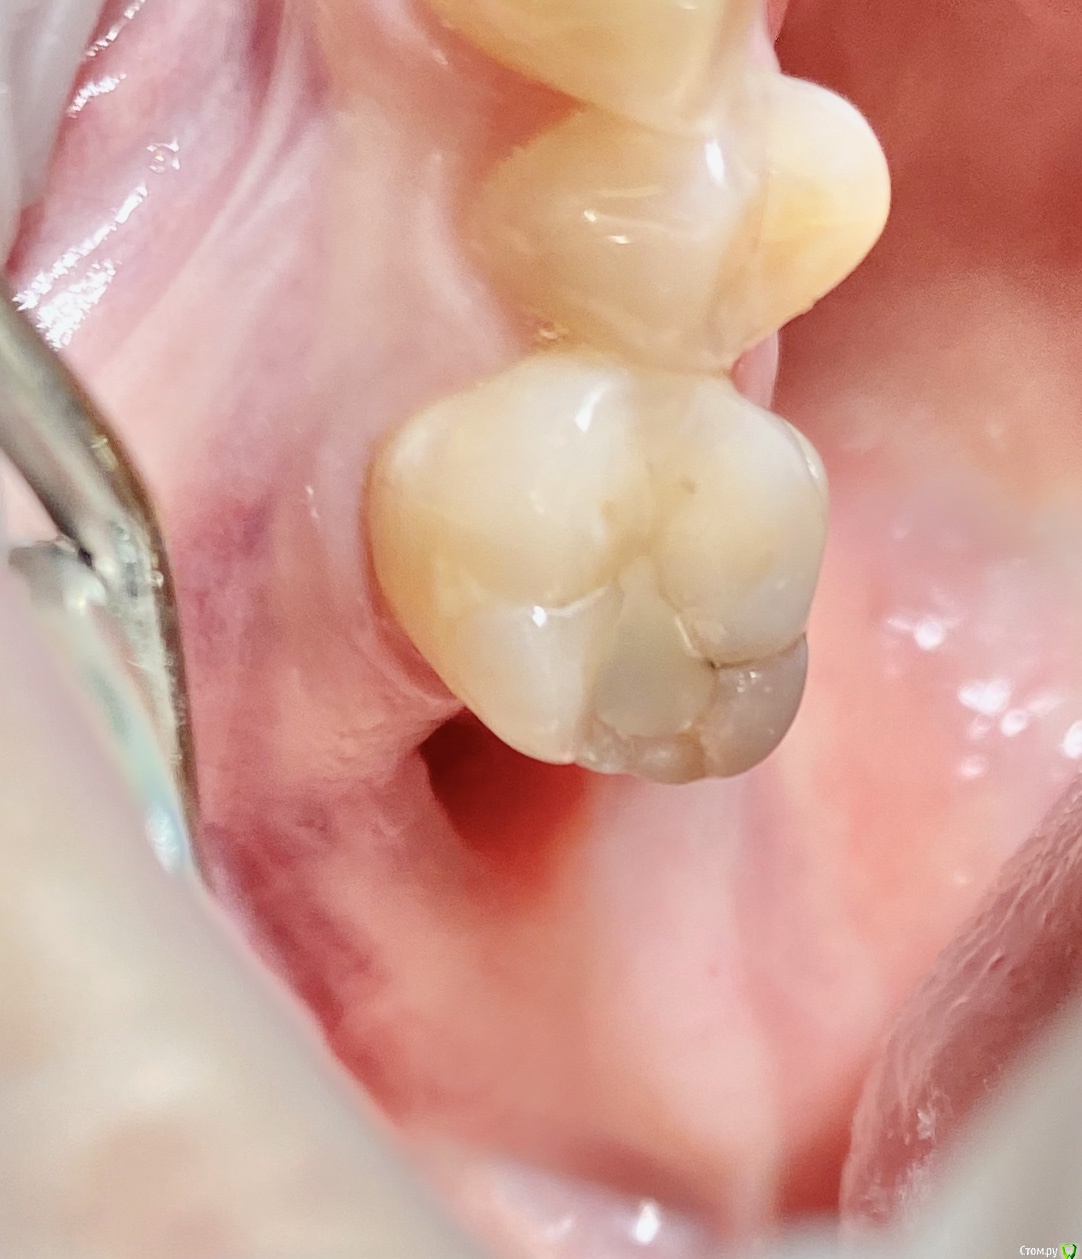

колесников Опубликовано 9 сентября, 2020 Поделиться Опубликовано 9 сентября, 2020 Бугор -это не только то ,что очевидно на поверхности 1 Ссылка на комментарий

колесников Опубликовано 11 сентября, 2020 Поделиться Опубликовано 11 сентября, 2020 Перемещение бугра для закрытия лунки. Вестибулярно прикрепленную не смещаем. Вестибулярно компактной пластинки нет 9 Ссылка на комментарий